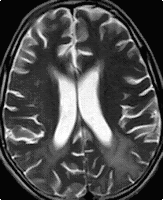

A case of chronic RRMS shows diffuse atrophy with periventricular white matter hyperintensity